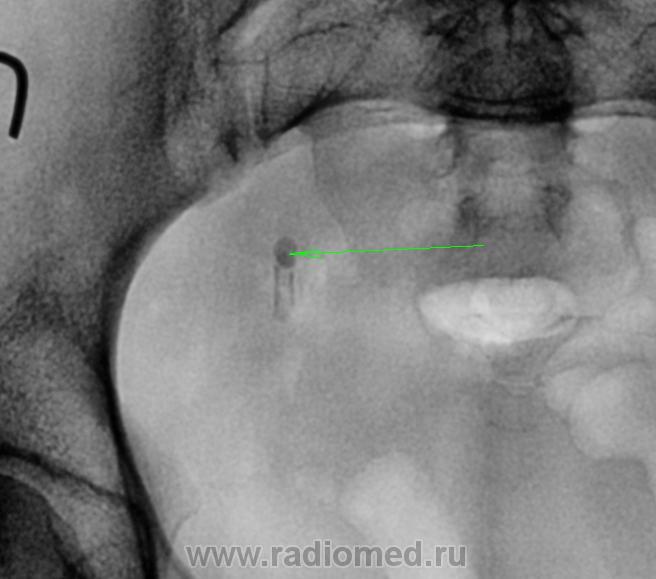

Пациентка с ноющей болью в поясничном отделе позвоночника, после проведения УЗИ(расширение ЧЛС справа) направлена к нам:

На урограммах чётко видно, конкремент н/3 правого мочеточника с гидронефрозом правой почки. А демонстрирую я это не прото так, чуть ниже конкремента идёт отложение по стенке мочеточника, я так понимаю уратов??? Ваше мнение?

Итак, в дистальной трети правого мочеточника визуализируется конкремент (рентгеноположительный), неоднородной структуры, с отдельными "более плотными" включениями.

Но, что это за две "параллельные полосочки" дистальнее тени конкремента? Я не думаю, что "сие" является отложением уратов "по стенке мочеточника".

На мой взгляд, ниже "тени рентгеноположительного конкремента", располагается другой (рентгеноотрицательный) конкремент, который, как и проксимальный является "обтекаемым". По всей видимости, то, что мы видим в виде параллельных полосочек - это отложение "более плотных" компонентов солей на внешней поверхности рентгеноотрицательного конкремента.

Совершенно верно. И не факт, что они всегда были "рядом". Возможно, "верхний" спустился недавно, и встал рядом с рентгеноотрицательным, что и привело, возможно, к клинике почечной колики.

В виде курьёза здесь можно предположить, что нижний камень имеет трубчатую форму – формировался в мочеточнике, на стенках. И если именно в том месте, где мы его видим, извлечь его просто так вряд ли удастся: видимо придётся иссекать часть мочеточника. Структура его, конечно, не уратная (ураты – рентгенонегативны) наиболее вероятны оксалаты.